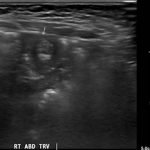

A segment of bowel within the right abdomen that measured approximately 1.6 x 1.5 cm transaxially. It demonstrated a hypoechoic edematous outer loop of bowel (blue arrow) and hyperechoic compressed loop of bowel telescoping within (red star), this is known as the “target sign.”

Intussusception is the invagination or telescoping of part of the intestine into itself. It is the most common cause of intestinal obstruction in children younger than 2 years.1 Ninety-five percent are ileocolic but any part of the small or large intestine can be involved.2 Abdominal pain is the most common symptom.3 Patients classically experience cyclic episodes (10 – 15 minutes) of severe abdominal pain. During these painful episodes, patients are often described as drawing the legs up to the abdomen and screaming in inconsolable pain. Ultrasound is operator dependent, however the sensitivity and specificity for intussusception approaches 100% with an experienced ultrasonographer.4 A good history and physical exam remain important, as the appearance of a “target sign” in the right lower abdomen can also be seen in appendicitis, caused by an appendixwith an appendicolith.